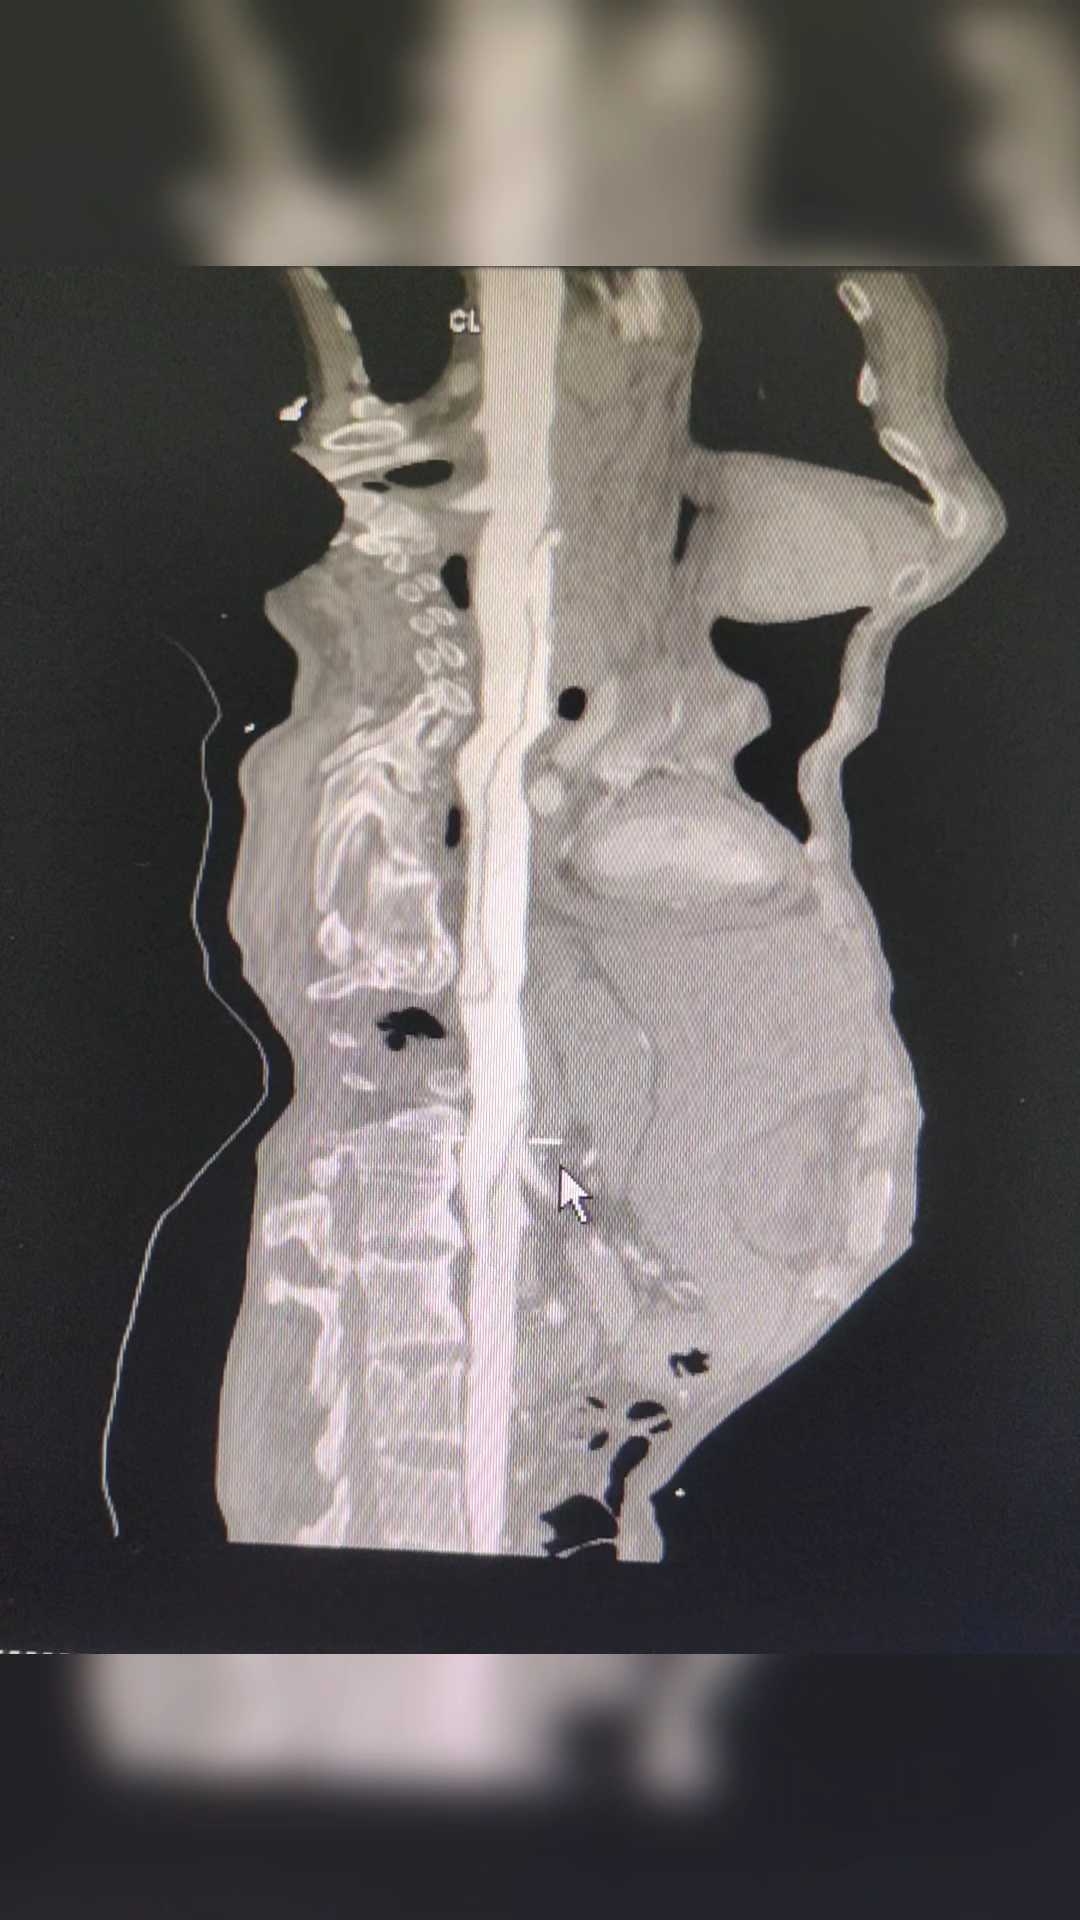

第二天,我们又去查了一个CTA。

主动脉夹层!

这个结果,是不是有点意外?因为症状不典型,如果不查CT,只按心脏的问题处理,那就麻烦大了!

急性 主动脉夹层 最典型症状为突发性剧烈胸/背疼痛,通常会伴有低血压和休克,其他特征性临床表现为心包积液、主动脉瓣反流和冠状动脉受累等。但是这个患者的胸痛不是很重,也没有低血压,双上肢的血压也没有明显的差距!特征性的表现,也就是心包积液了!